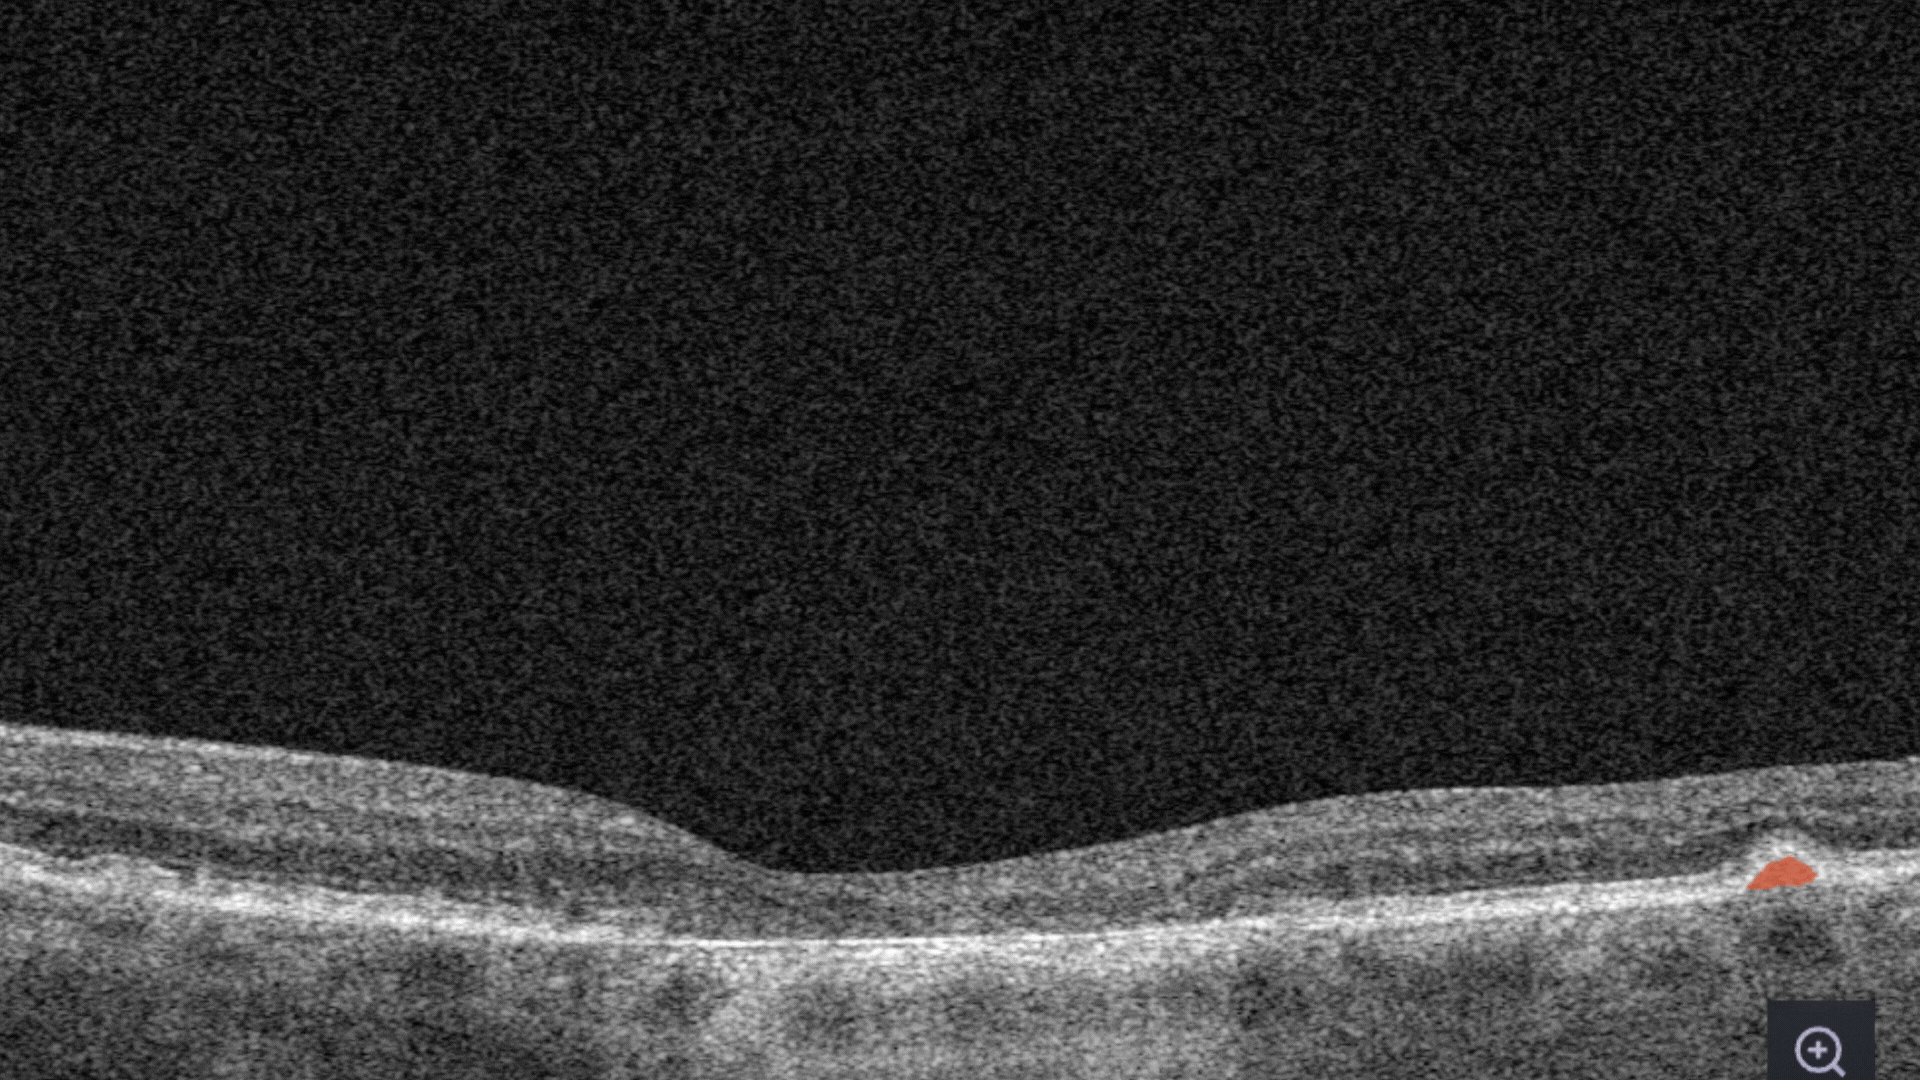

Ellipsoid zone disruption is the changes in the photoreceptor layer can be identified as a disruption or defect in the ellipsoid zone (EZ).

RPE Disruption is the disruption of the Retinal Pigment Epithelium layer

Subretinal fluid corresponds to the accumulation of a clear or lipid-rich exudate (serous fluid) in the subretinal space, i.e., between the neurosensory retina (NSR) and the underlying retinal pigment epithelium (RPE), in the absence of retinal breaks, tears, or traction